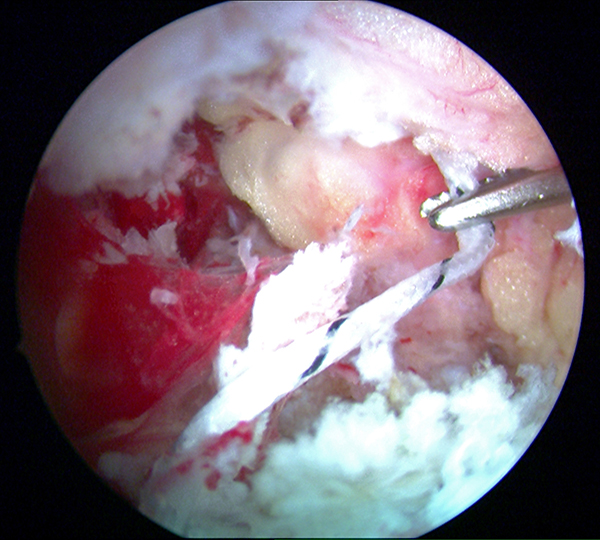

Abbildungen 9-11, Video 3

In maximaler Plantarflexion des Fußes wird die FHL-Sehne durch kräftigen Zug an den Fadenenden nach kranial mobilisiert und soweit wie möglich distal tenotomiert. Die Tenotomie kann mit einer feinen Schere, einem Punch oder mit einem 11er Skalpell über den posteromedialen Arthroskopiezugang durchgeführt werden. Für die Tenotomie sollte eine gute Übersicht vorhanden sein, um eine Verletzung des Gefäß-Nerven-Bündels zu vermeiden. Der Sehnenstumpf wird aus dem posteromedialen Portal ausgeleitet.